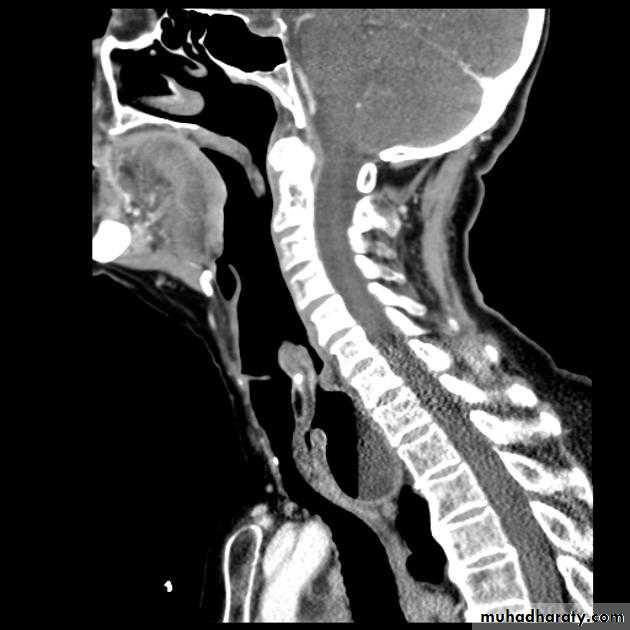

IMAGING OF DYSPHAGIA

Benign vs. malignant Causes Specific locationContrast study EUS CT